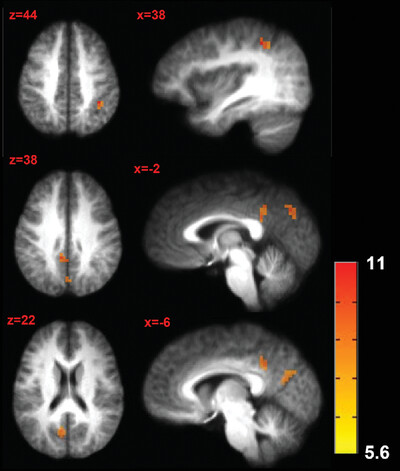

See our new article out in NeuroImage: Tonic pain alters functional connectivity of the descending pain modulatory network sciencedirect.com/science/articl…